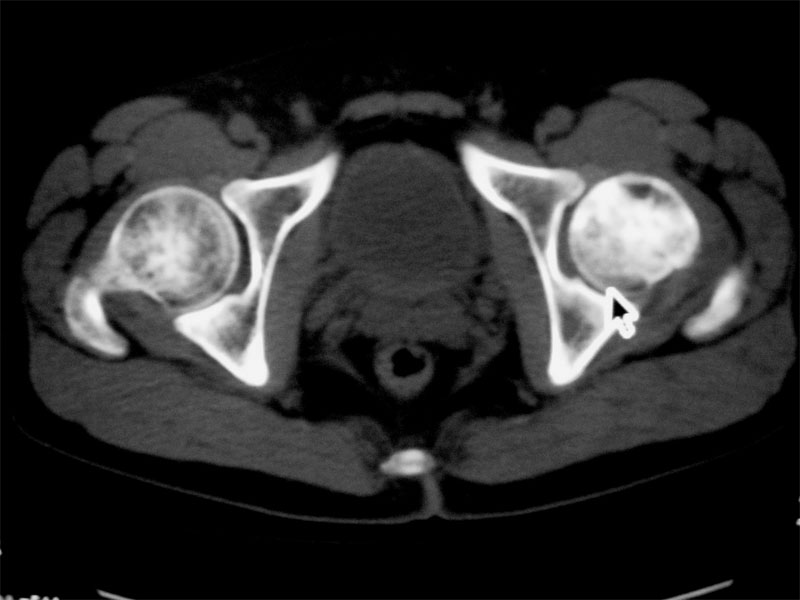

左侧髋关节少量积液.上传骨窗

建议提供骨窗资料

考虑左股骨头缺血性坏死;右股骨上段良性骨肿瘤,考虑成软骨细胞瘤可能。建议上传骨窗。

考虑左侧股骨头坏死。建议提供骨窗资料。